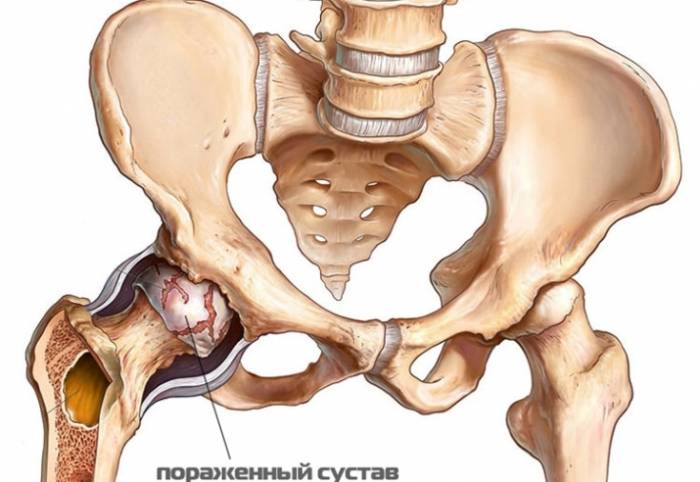

Тазобедренный сустав образуют головка бедренной кости и вертлужная впадина, которая формируется подвздошной, лобковой, седалищной костями. Головка покрыта гиалиновым хрящом, благодаря гладкости которого она свободно скользит по поверхности вертлужной впадины во время движения нижней конечности.

Формированию рассекающего остеохондрита тазобедренного сустава предшествуют следующие изменения. Сосуды, которые питают структуры тазобедренного сустава под действием выше описанных патологических факторов тромбируются и спазмируются. На фоне таких процессов классически нарушается кровоснабжение структур сустава – в первую очередь, хрящевой. Образуется зона асептического некроза – сперва она может быть точечной, далее увеличивается в размерах. Особенности хряща таковы, что его омертвение проходит в виде очага, который затем отделяется от здоровых тканей и превращается в отдельное внутрисуставное тело. Какое-то время отколовшийся фрагмент хряща, словно на ниточке, соединяется со здоровыми хрящевыми тканями, далее и эта «перемычка» некротизируется, хрящевой фрагмент падает в суставную полость, при этом нередко блокируя тазобедренный сустав. Такая блокировка может быть преходящей, если суставному телу благодаря его гладкой поверхности удается выскользнуть из узкого места суставной полости. Даже небольшое суставное тело способно буквально поцарапать хрящ.

Выделены четыре стадии рассекающего остеохондрита тазобедренного сустава:

- первая – у пациента возникают чувство дискомфорта, которое может трансформироваться в неопределенные болевые ощущения без какой-либо четкой локализации, нередко они проявляются в виде дискомфорта. На рентгенограмме тазобедренного сустава можно обнаружить инородный фрагмент, который состоит из чередующихся участков мертвых и здоровых тканей. Также можно различить «перемычку», с помощью которой фрагмент соединяется с хрящом головки бедренной кости;

- 2 стадия– в синовиальной оболочке, которая выстилает тазобедренный сустав изнутри, появляются очаги воспаления, которые через довольно короткое время сливаются. На этой стадии впервые появляется боль в суставе. На рентгенологическом снимке видно отломавшийся осколок, при этом «перемычка», которая соединяет фрагмент хряща и суставную поверхность, истончается, но она сохранена;

- 3 стадия– на рентгенологическом снимке четко видно отделение некротического участка от суставного хряща головки бедренной кости. Именно на этой стадии патологических изменений развивается полноценная клиническая картина (в том числе блокировка сустава);

- 4 стадия– суставное тело свободно лежит в полости тазобедренного сочленения, но его размеры могут быть меньше, чем изначально, так как из-за движений головки, которая «гоняет» тело по полости, оно может крошиться.